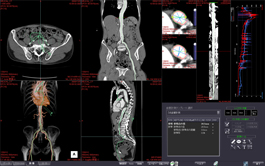

The Multi-Data Fusion protocol highlights spatial relationships between objects that can assist in planning surgical procedures.

This protocol is used to segment image masks of the hepatic artery, portal vein, hepatic vein using data of liver scanned with a contrast material and measure volumes including liver segments and lesions.